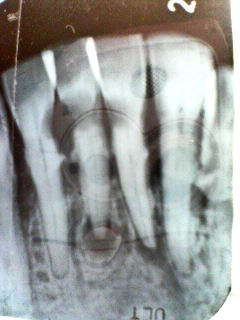

例えばこのレントゲン、

神経が通る穴、根管は左が湾曲し、右が根尖で右に振っています。

さらにやっかいなのが根管が異常に細いことです。

この根管を初めに示したような器具だけでは到底治療は上手くいきません。

そこで最新鋭(?)の器具を使用し、このように根管内に薬を詰めることができました。

でもこの治療は古典的(?)器具が無ければ成し遂げることができなかった、ということも付け加えておきます。

古いからダメ、新しいからイイ・・・ではなく、全ての器具の良い所取りをして治療に望むようにしています。